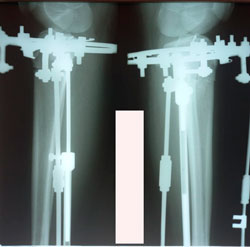

Исходник - 14 лет.

Дата операции - 16.12.2020